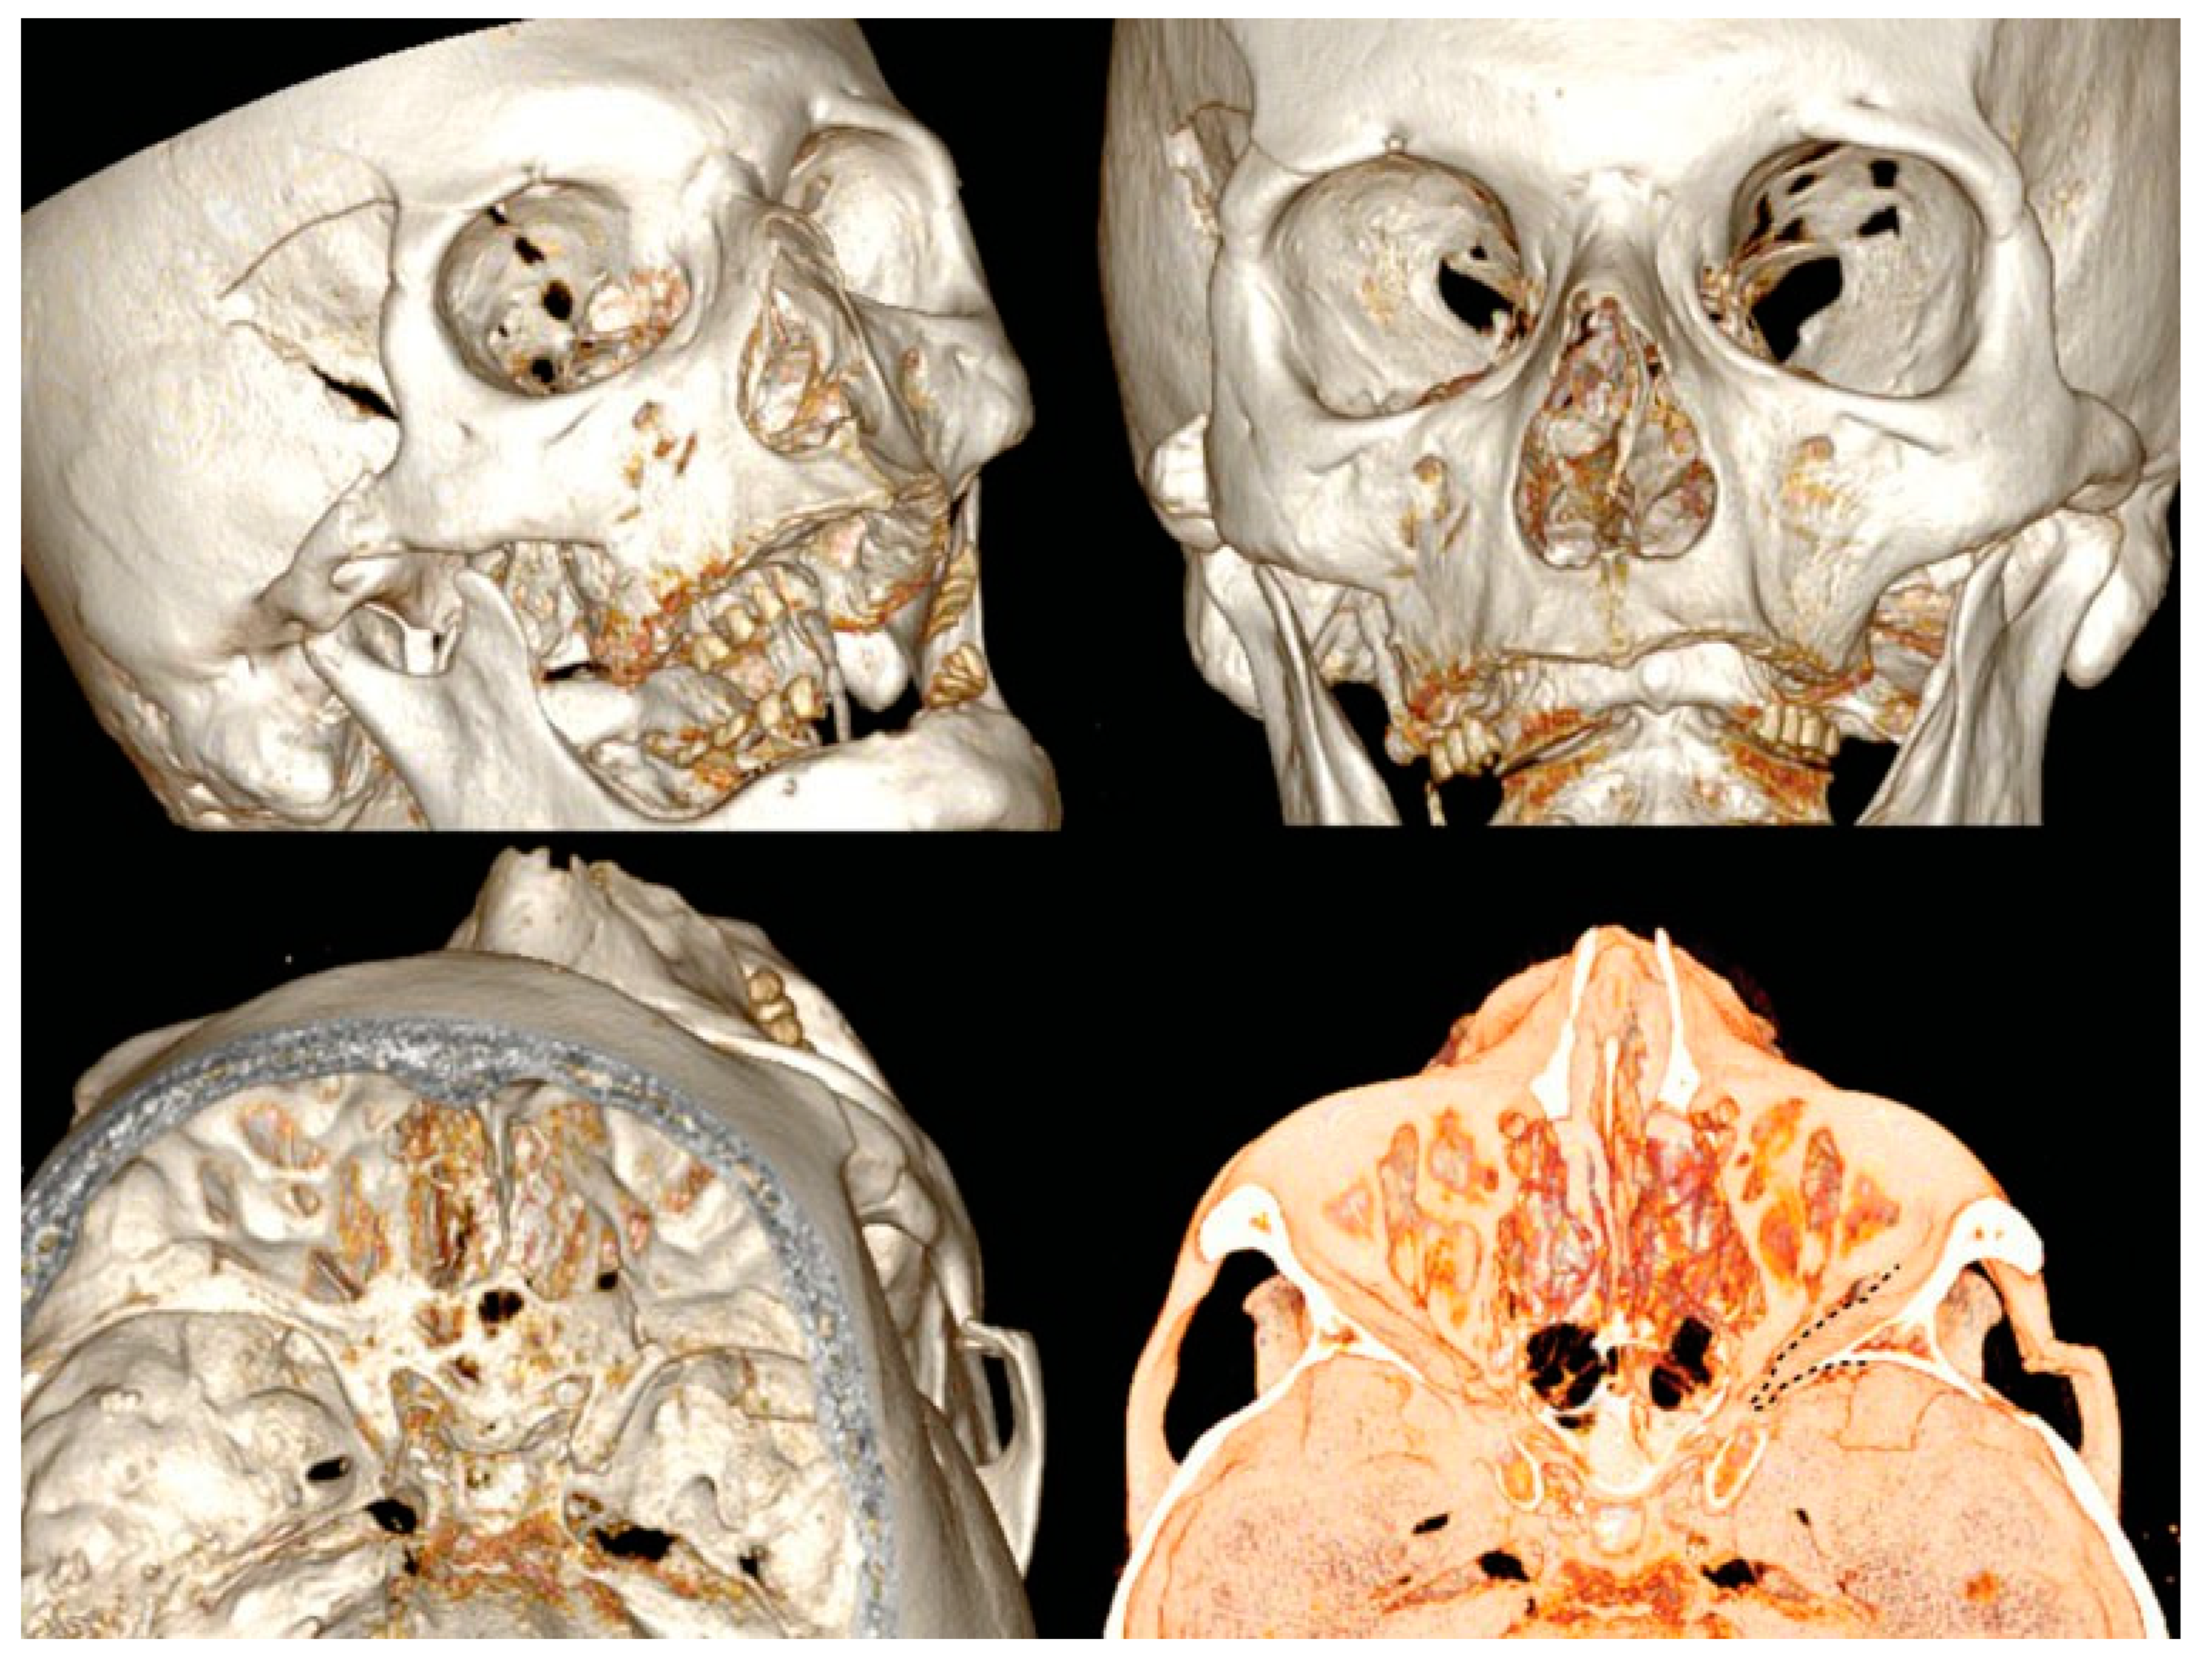

A new spiral craniomaxillofacial CT scan with coronal, sagittal, and three-dimensional (3D) reconstruction was performed the following morning. The imaging examination revealed a displacement of the lateral wall of the right SOF which was reduced in amplitude. The fracture was classified as a rare frontosphenotemporal fracture, according to Pellerin et al. [8], that is frequently associated with visual impairment (Figure 2). This pattern of fracture is characterized by the preservation of integrity of the lateral orbital wall and its whole dislocation. A thin layer of epidural blood of approximately 7 mm at the middle temporal fossa was also noticed, adjacent to the greater wing of the sphenoid bone.

Figure 2.

3D CT scan reconstruction showing four different projections of frontosphenotemporal Pellerin et al fracture pattern; note in frontal view (up right), SOF size reduction caused by medial displacement of the entire right lateral orbital wall; the black dashed line in the intracranial view (down right) shows the medial collapse of lateral orbital wall into the SOF. CT, computed tomography; SOF, superior orbital fissure; 3D, three-dimensional.